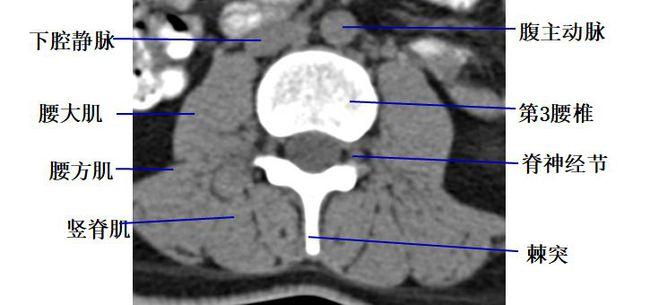

经腰椎椎间盘的横断层面(ct)